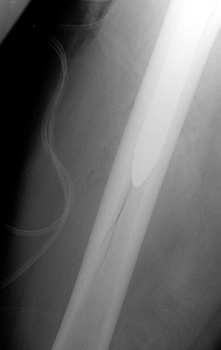

Intraoperative fracture of the femur at the tip of the femoral stem.